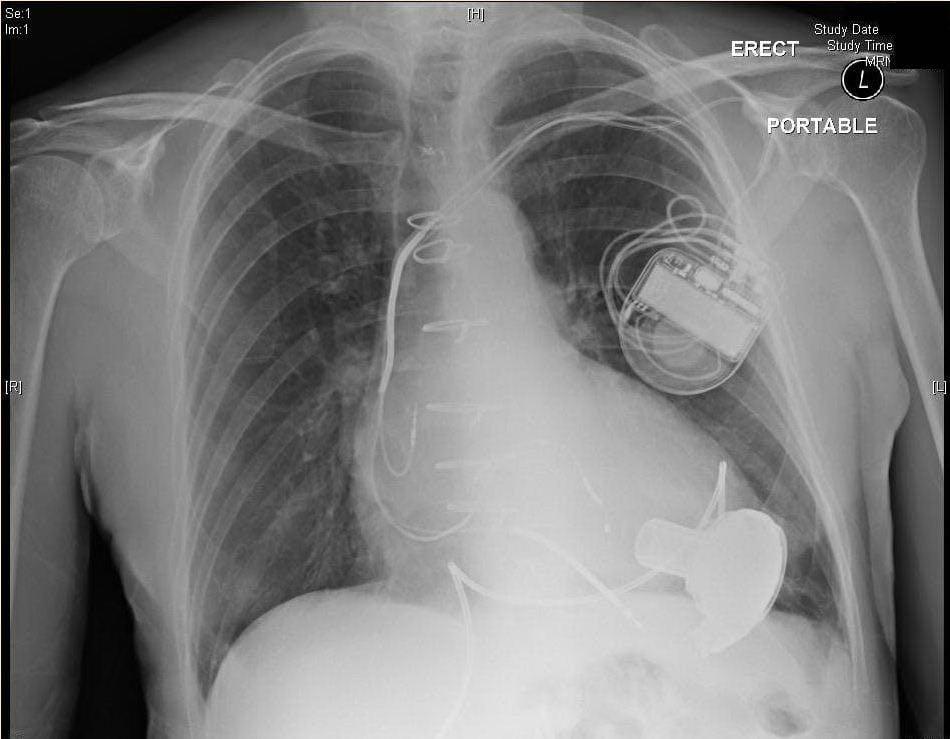

«Из анамнеза было известно, что он страдает гипертонической болезнью более 5 лет, перенес инфаркт миокарда, после чего через некоторое время начал чувствовать резкое ухудшение самочувствия. С 2019 года участились госпитализации по неотложным показаниям по поводу острой декомпенсации сердечной недостаточности и был имплантирован кардиовертер-дефибриллятор из-за частых приступов аритмии», — говорится в сообщении.

«Таким пациентам показана имплантация устройства — LVAD HEART MATE 3. Устройство предоставляется бесплатно для пациента благодаря программе «Здоровье киевлян», — сообщили в КГГА.